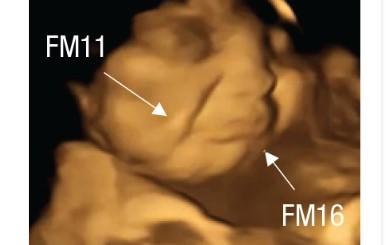

A team of scientists studied 4D ultrasound scans of 100 pregnant women and discovered that babies exposed to carrot flavors showed "laughter-face" responses.

Those exposed to kale flavors, in contrast, showed more "cry-face" responses.